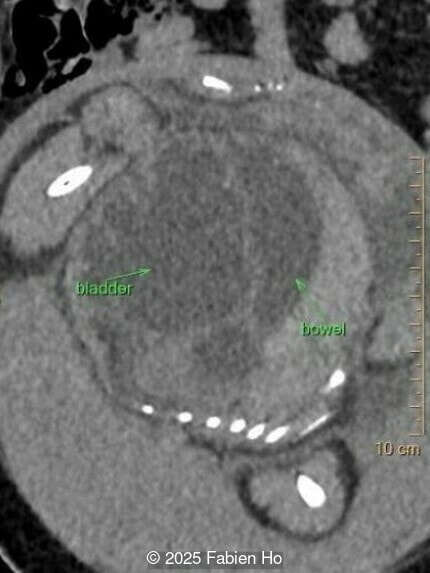

Axial image of the fetal pelvis

Image 14 Axial image of the fetal pelvis

Our prenatal ultrasound revealed a male fetus with megabladder, dilation of both ureter and kidneys, and thinned kidney parenchyma consistent with Lower Urinary Tract Obstruction (LUTO).  Additional findings suspected on ultrasound and confirmed on computed tomography included:

• Suspicion of dilated bowel in the left flank, in addition to dilated urinary tract